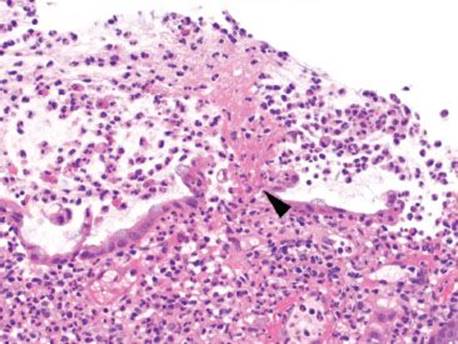

Figure 4.82 Pseudomembranous pattern, early. Higher magnification of the previous case shows the fibrin (arrowhead) erupting from the colonic surface amidst numerous neutrophils.

Figure 4.83 Pseudomembranous pattern, early. The eruptive pseudomembrane is hard to miss, even at low magnification. Interestingly, the background mucosa sometimes shows little to no change, as seen here.